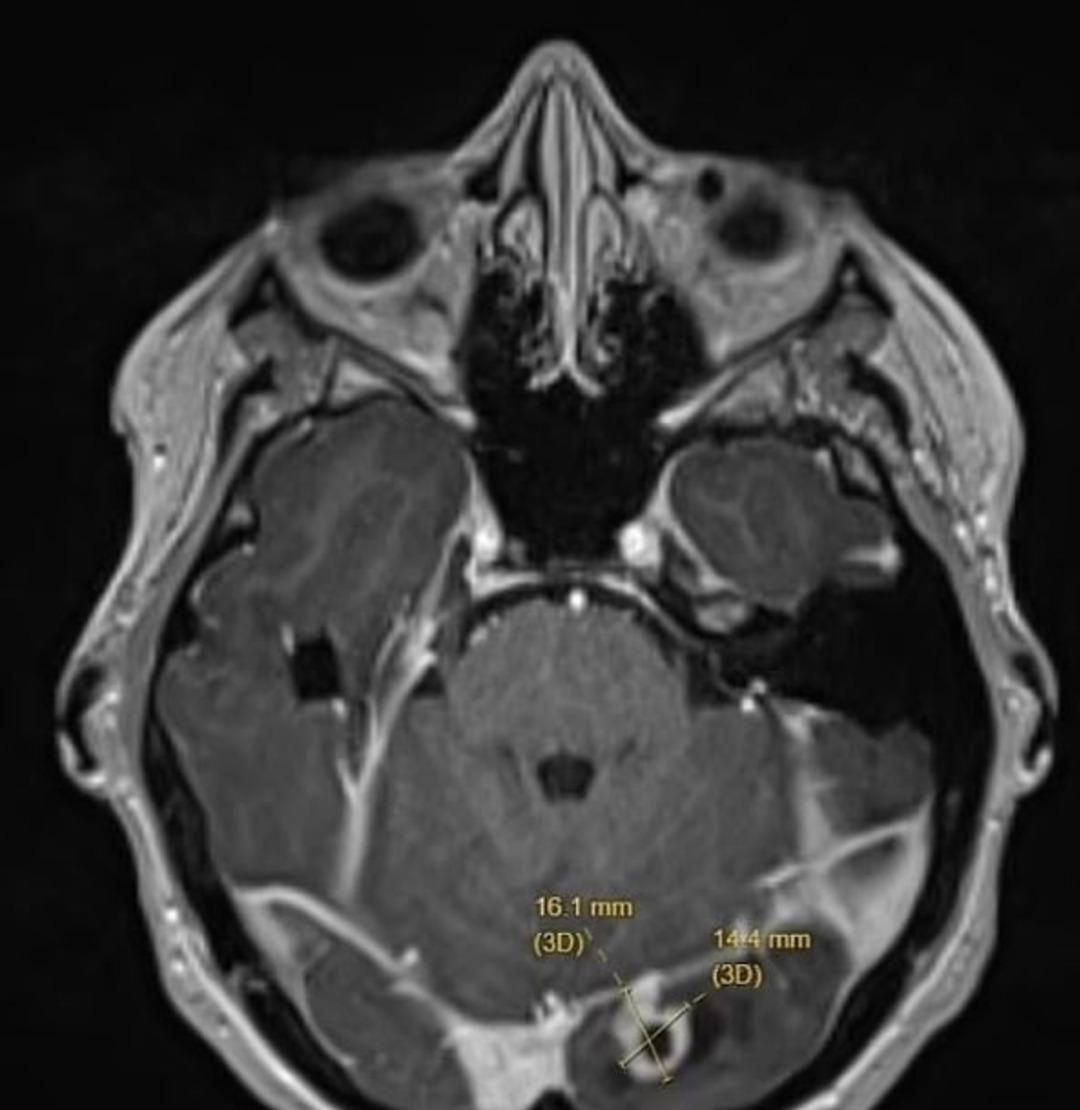

Doğumdan 3 ay sonra bir futbol maçında geçirdiği nöbet sonrasında beyninde sessizce büyüyen bir tümör olduğu ortaya çıktı. Kanserli olmayan hücre, hamilelikte hormonel değişimlerin tümörü tetikleyerek nöbet başlatmış olabileceği düşünülüyor. Ash ise baş ağrılarının ve gözünde önde beliren ışık parlamalarının çocukluğundan beri yaşandığını fakat bunun tümörle bağlantısı olduğunu yeni fark ettiğini söyledi.